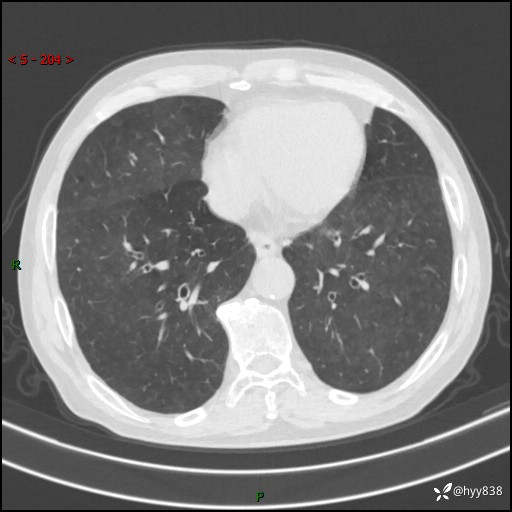

儿女怕老人寂寞,养了两只鹦鹉,呼吸科主任问我典不典型---结果公布~

武医生 等 4 位达人已点赞患者性别:男

患者年龄:71岁

主诉:喘气半年余,咳嗽乏力伴味觉减退2月余

简要病史:者半年前左右无明显诱因出现呼吸困难,轻微运动后出现喘气,未予以重视。2月余前受凉感冒后出现咳嗽,咳白色泡沫痰,不易咳出,于当地医院行输液治疗,未见明显好转,并感觉全身乏力,体力下降,并感口苦,味觉减退。近10余天前感咳嗽喘气加重,咳白色泡沫痰,不易咳出,口苦,味觉减退加重。为进一步检查及治疗,入我院就诊,门诊以“呼吸困难”收入院治疗。 起病以来,患者精神,睡眠,饮食欠佳,大小便可,体力下降明显,体重稍下降。

辅助检查:CT

临床诊断:呼吸困难

胸部CT平扫